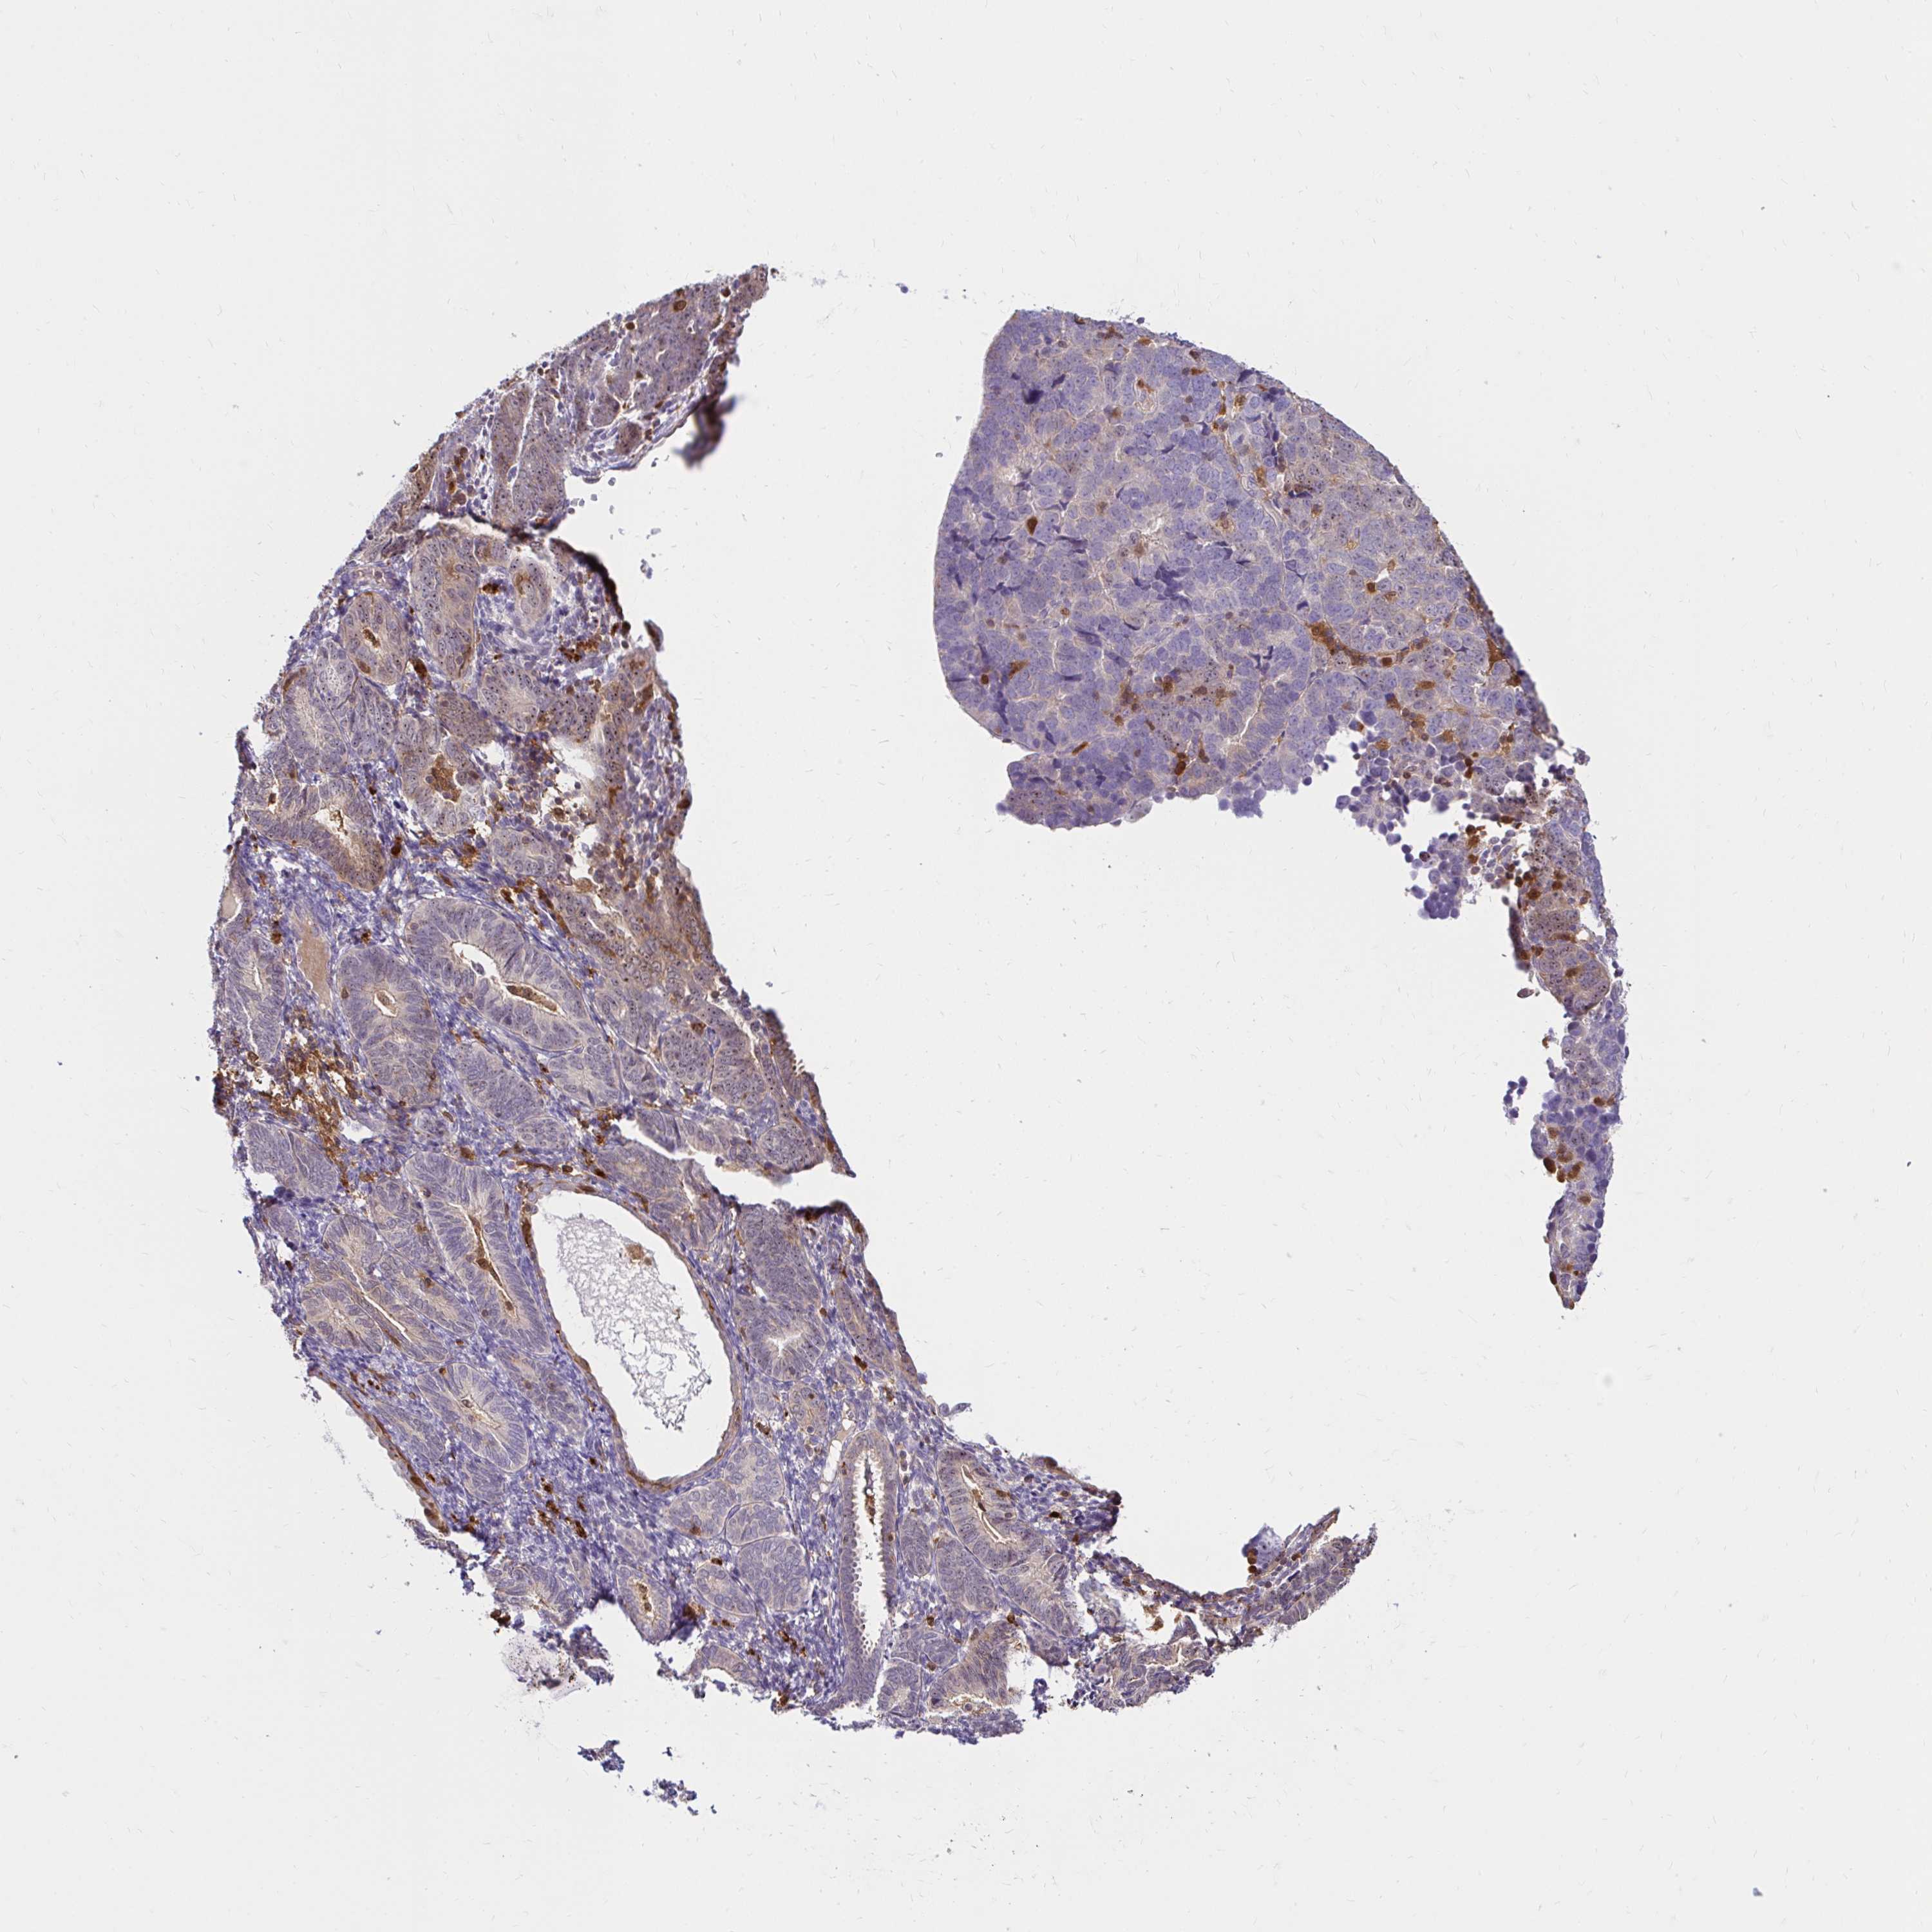

ENDOMETRIAL CANCER - Protein expressioni

A mouse-over function shows sample information and annotation data. Click on an image to view it in a full screen mode. Samples can be filtered based on level of antibody staining by selecting one or several of the following categories: high, medium, low and not detected. The assay and annotation is described here.

Note that samples used for immunohistochemistry by the Human Protein Atlas do not correspond to samples in the TCGA dataset.

Antibody stainingi

Antibody staining in the annotated cell types in the current human tissue is reported as not detected, low, medium, or high, based on conventional immunohistochemistry profiling in selected tissues. This score is based on the combination of the staining intensity and fraction of stained cells.

Each image is clickable and will lead to virtual microscopy that enables deeper exploration of all samples and also displays staining intensity scores, fraction scores and subcellular localization as well as patient and tissue information for each sample.

Antibody HPA049074

Antibody HPA054496

Antibody CAB006853

Antibody CAB015948

Staining

High

Medium

Low

Not detected

Intensity

Strong

Moderate

Weak

Negative

Quantity

>75%

75%-25%

<25%

None

Location

Nuclear

Cytoplasmic/membranous

Cytoplasmic/membranous,nuclear

Adenocarcinoma, NOS

Carcinoma, NOS

Adenocarcinoma, metastatic, NOS

Neoplasm, malignant, NOS